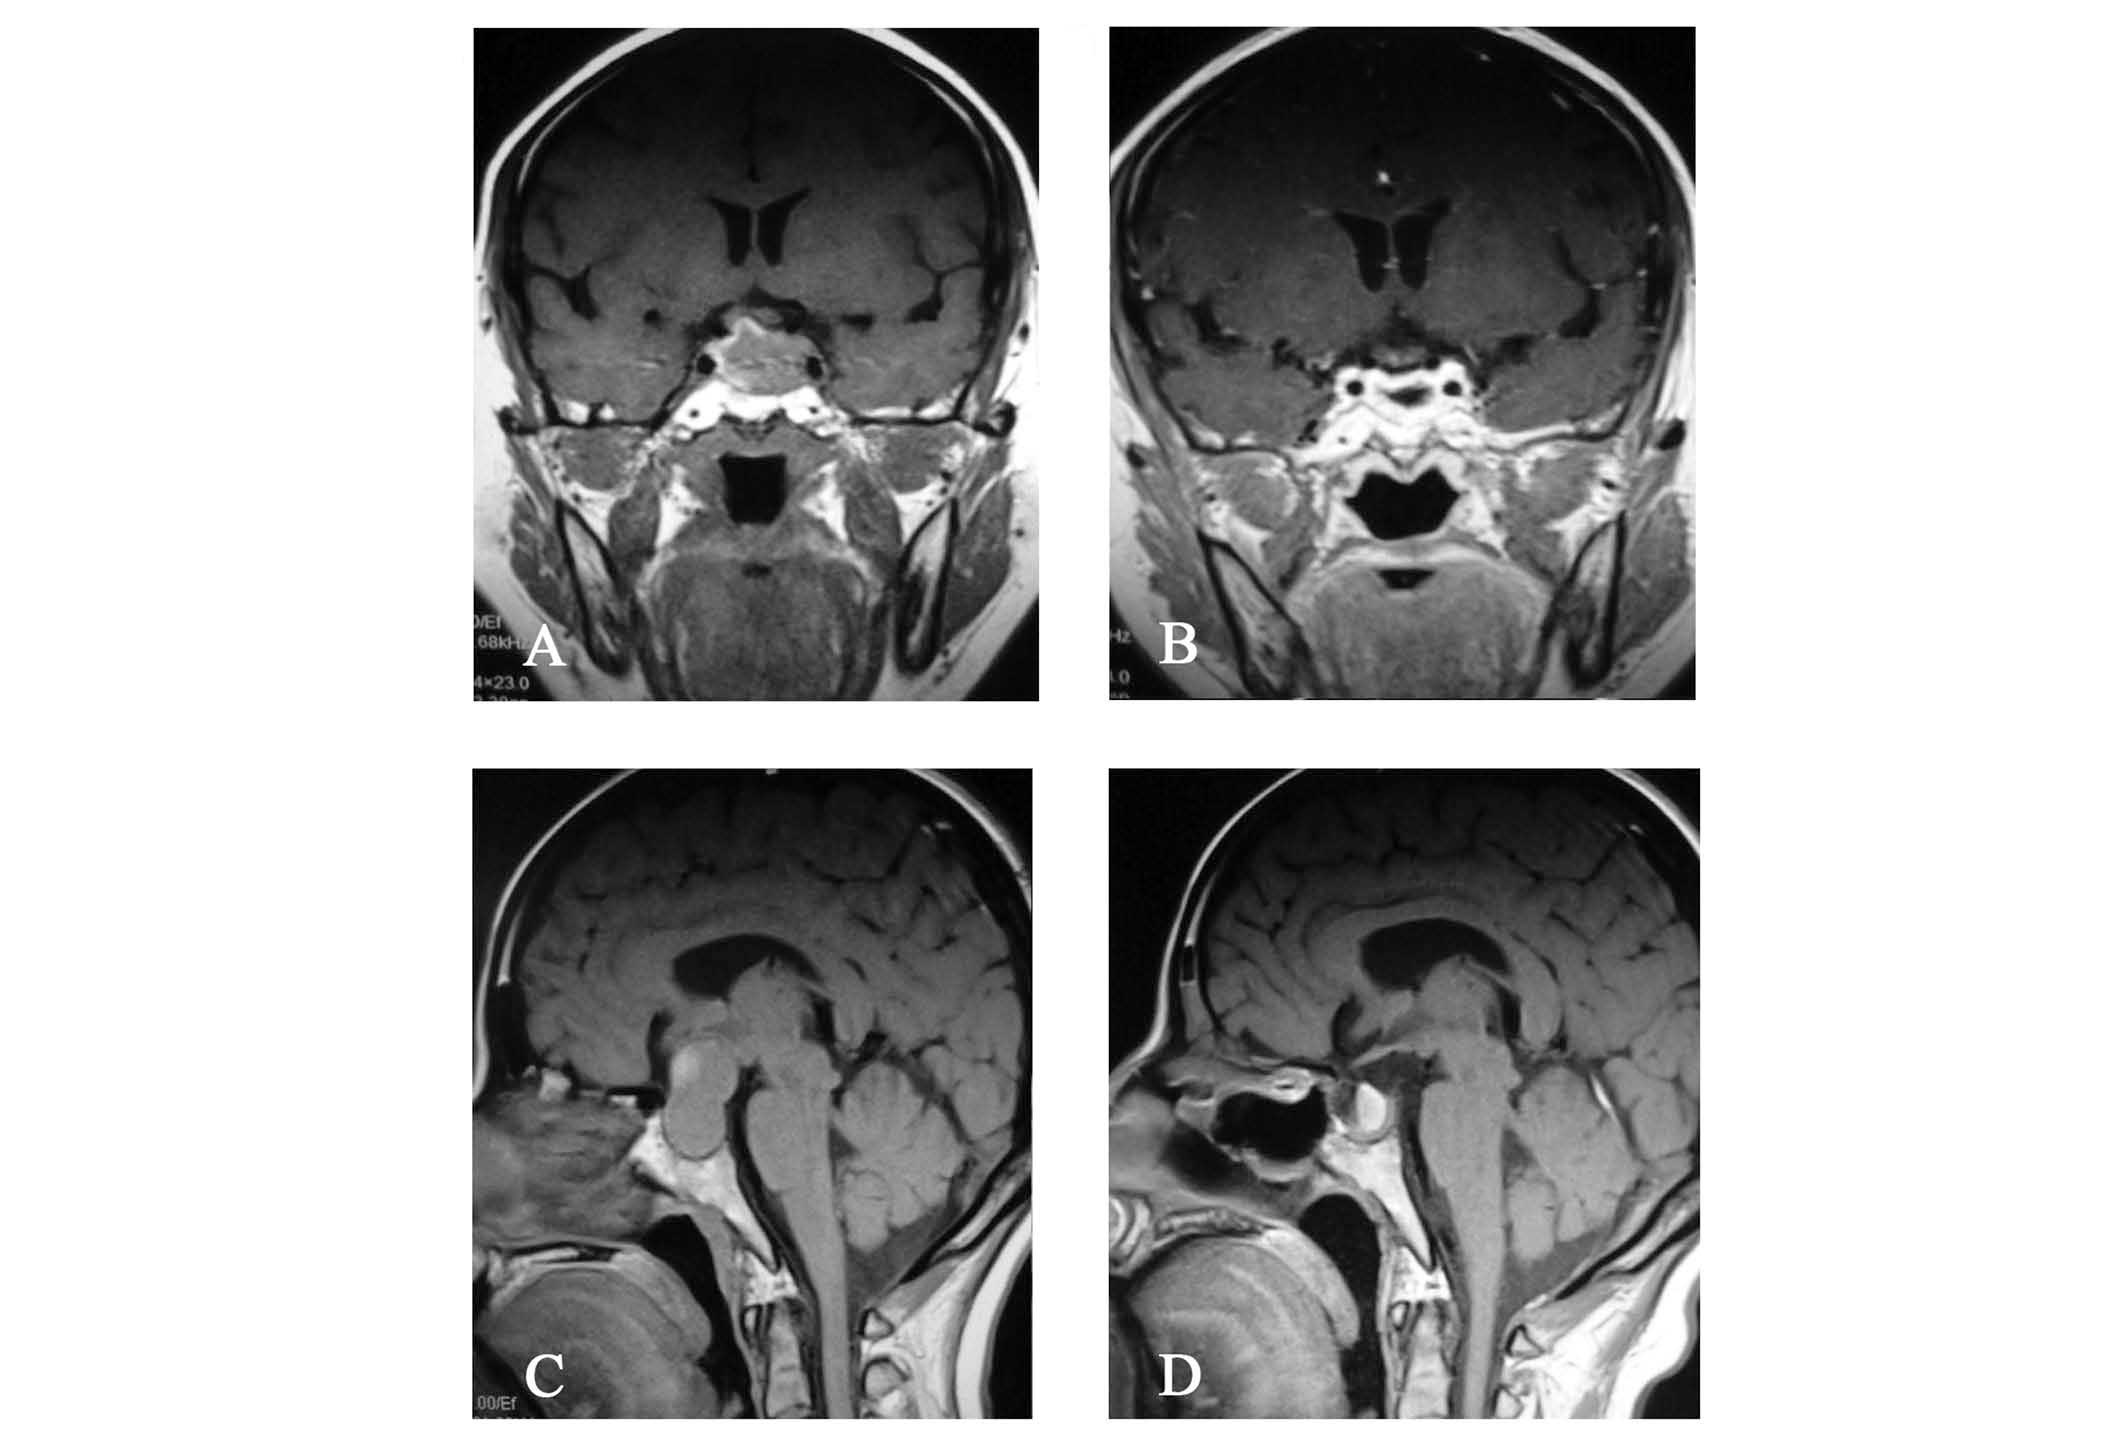

Nasal examination was normal. The right pupil size was 2.5 mm (normal range, 2.5–5.0 mm) with normal papillary reflex and the left pupil size was 4.0 mm with no papillary reflex. Visual acuity and visual field of the two eyes were normal. No strabismus or diplopia were observed and the eye movement was normal. Endocrinological investigations demonstrated decreased adrenocorticotropic hormone (ACTH; 1.10 pg/ml, normal range, 7.20–63.60 pg/ml) and luteinizing hormone (LH; 2.78 mIU/ml, normal range, 15.90–54.00 mIU/ml), normal thyroid stimulating hormone (TSH; 1.56 mIU/ml, normal range, 0.40–4.78 mIU/ml), follicle-stimulating hormone (FSH; 15.96 mIU/ml, normal range, 23.00–116.30 mIU/ml), growth hormone (GH; 0.43 ng/ml, normal range, 0.12–9.88 ng/ml) and prolactin (PRL; 2.48 ng/ml, normal range, 1.80–20.30 ng/ml) (Table I). Magnetic resonance imaging indicated a sellar tumor extended into the left cavernous sinus and a non-pneumatized sphenoid sinus (Fig. 1A). Following the aforementioned physical and clinical examinations, the tumor was excised under general anesthesia via the endoscopic transsphenoidal route. Skull base closure was achieved with a combination of autologous fascia lata grafts, fibrin glue and nasoseptal flap(s). The excised tumor was subjected to histopathology, which indicated a diagnosis of pituitary adenoma.

Postoperatively, the patient developed transient diabetes insipidus for six days, however no other complications, such as intracranial infection, cerebrospinal fluid leakage, intracerebral hemorrhage or cranial nerve palsies, were observed. Blepharoptosis recovered on day 13 after surgery. A magnetic resonance image captured one year following the surgery demonstrated that total resection was achieved (Fig. 1B). No recurrence was observed prior to the termination of follow-up, two years after the surgery was performed.

The nasal examination was normal. The patient’s visual acuity (normal range, >1.0) was measured at 4 m using a retroilluminated logarithm of the minimum angle of resolution chart with tumbling-E optotypes (Precision Vision, La Salle, IL, USA), which revealed that the [visio oculus sinister (VOS)] in the left eye was counting fingers/30 cm and the [visio oculus dexter (VOD)] in the right eye was 0.3. Additionally, a visual field defect of bitemporal hemianopia was observed. Endocrinological investigations demonstrated elevated PRL (70.43 ng/ml, normal range, 1.80–20.30 ng/ml), decreased FSH (4.09 mIU/ml, normal range, 23.00–116.30 mIU/ml) and LH (0.39 mIU/ml, normal range, 15.90–54.00 mIU/ml), and normal TSH (3.29 mIU/ml, normal range, 0.40–4.78 mIU/ml), GH (0.31 ng/ml, normal range, 0.12–9.88 ng/ml) and ACTH levels (21.09 pg/ml, normal range, 7.20–63.60 pg/ml) (Table I). Magnetic resonance imaging indicated the presence of a sellar tumor, which had extended into the suprasellar cistern and caused compression of the optic nerves and optic chiasma, as well as a non-pneumatized sphenoid sinus (Fig. 1C). The surgical technique utilized in case two was identical to that used in case one; the intraoperative view is shown in Fig. 2. Subsequent histopathological examination of the lesion indicated a diagnosis of pituitary adenoma.

Postoperatively, the patient developed transient diabetes insipidus for 11 days. Prior to discharge (13 days following surgery), visual acuity was determined to be 0.8 VOS and 1.0 VOD, and visual field was fully recovered. Magnetic resonance imaging indicated that total resection of the tumor had been achieved, however, a hematoma was observed in the posterior pituitary fossa with no clinical symptoms (Fig. 1D). No additional complications were observed at the most recent follow-up examination in February 2014.